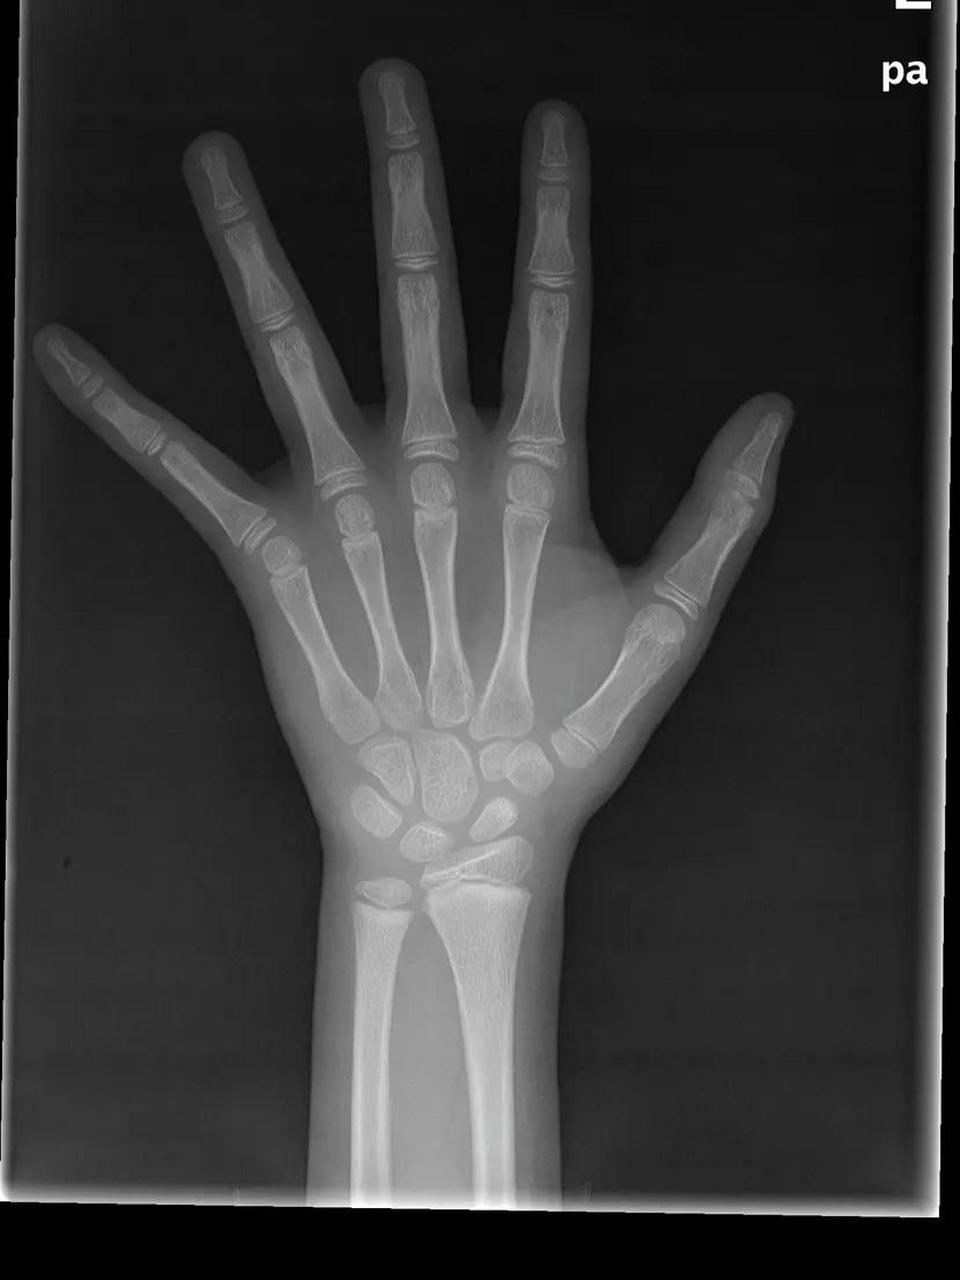

9岁女孩骨龄片

请帮忙看一下这个片子的骨龄(女孩)是几岁

多久拍一次骨龄合适这骨龄有9岁吗

教你简单识别孩子的骨龄片

骨龄图

骨龄图谱_女ppt

中国儿童标准骨龄片